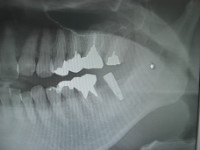

パンチアウトにてインプラント埋入

今日のオペはCT診査の結果、骨幅骨高ともに十分ある症例でしたので、パンチアウトにて歯肉をくり抜き問題なくインプラントを埋入いたしました。

極力外科的な侵襲を少なくしてオペが終了できたと思います。